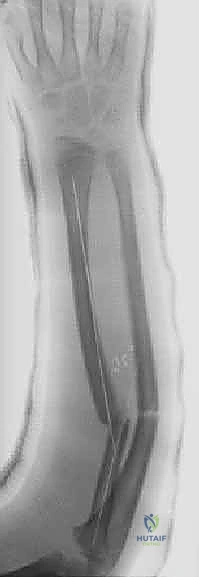

تُعد تقنية التثبيت بالمسامير المرنة داخل النخاع (Flexible Intramedullary Nailing - FIN) أو مسامير التيتانيوم المرنة (Titanium Elastic Nails - TENs) المعيار الذهبي (Gold Standard) لعلاج كسور الساعد غير المستقرة لدى الأطفال. والأستاذ الدكتور محمد هطيف هو رائد هذه التقنية في اليمن.

مبدأ عمل المسامير المرنة

على عكس الشرائح والمسامير التقليدية (Plates and Screws) التي تتطلب شقوقاً جراحية كبيرة وتؤدي إلى تقشير السمحاق (مما يضعف التروية الدموية للعظم)، تعمل المسامير المرنة بمبدأ مختلف تماماً.

يتم إدخال مسمارين مرنين (عادة من التيتانيوم أو الصلب الطبي المقاوم للصدأ) داخل التجويف النخاعي (Marrow Canal) للعظم. يتم ثني هذه المسامير مسبقاً بواسطة الجراح لتشكيل قوس. عندما يتم إدخالها في العظم، فإنها تعمل بمبدأ "التثبيت ثلاثي النقاط" (Three-Point Fixation). تولد المسامير المرنة قوة شد داخلية تدفع أجزاء العظم المكسور نحو بعضها البعض، مما يوفر استقراراً حيوياً ميكانيكياً (Biomechanically Stable) يسمح بتكوين الكالس (Callus) وشفاء العظم بسرعة فائقة.

مميزات تقنية المسامير المرنة مع أ.د. محمد هطيف:

- تدخل جراحي طفيف (Minimally Invasive): شقوق جراحية صغيرة جداً (1-2 سم) لإدخال المسامير، مما يعني ندبات شبه معدومة وألماً أقل بكثير بعد الجراحة.

- الحفاظ على التروية الدموية: عدم فتح موقع الكسر (في معظم الحالات) يحافظ على الورم الدموي الخاص بالكسر (Fracture Hematoma) والسمحاق، مما يسرع من التئام العظم بشكل طبيعي.

- الحفاظ على صفائح النمو: يتم إدخال المسامير بحذر شديد لتجنب إصابة صفائح النمو المسؤولة عن طول العظم مستقبلاً.

- نتائج تجميلية ووظيفية ممتازة: استعادة كاملة للانحناء الطبيعي للكعبرة وحركة الساعد.